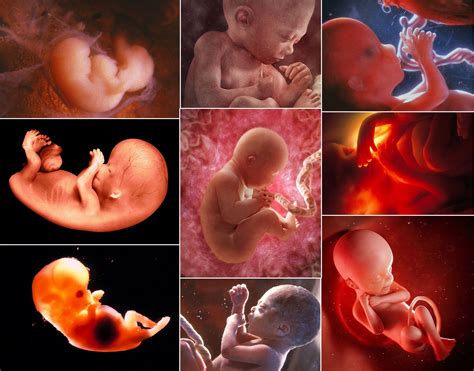

Na samom začiatku tehotenstva, ktoré sa počíta od prvého dňa poslednej menštruácie, dochádza k ovulácii a následnému oplodneniu vajíčka spermiou. Oplodnené vajíčko putuje do maternice a uhniezdi sa na jej výstelke. Z neho sa začínajú vyvíjať placenta, pupočná šnúra a plodové obaly. V tomto štádiu sa embryo podobá na žubrienku a jeho srdiečko sa začína deliť na predsiene a komory. Hoci embryo meria len niekoľko milimetrov, už sa mu vyvíjajú základné orgány ako obličky, pľúca a črevá.

Počas druhého mesiaca sa embryo rýchlo mení a začína sa podobať na bábätko. Vytvára sa tvárička s ústnym otvorom, vyvíjajú sa zárodky horných a dolných končatín, ktoré už majú viditeľné pršteky, a formujú sa očné viečka a základ nosa a jazyka. Srdiečko už bije a je detegovateľné ultrazvukom. Vznikajú všetky hlavné väčšie orgány, aj keď ich vývoj ešte nie je dokončený. Embryo robí spontánne pohyby, ktoré však matka ešte necíti. Placenta sa intenzívne vyvíja a zabezpečuje výživu pre plod. Symptómy tehotenstva sú v tomto období zvyčajne výraznejšie.

Tretí mesiac predstavuje koniec prvého trimestra. Dieťa je už oficiálne nazývané plodom. Maternica sa zväčšuje a na konci mesiaca je ju možné nahmatať nad lonovou kosťou. Plod rýchlo rastie, dosahuje dĺžku okolo 6-7,5 cm a váži približne 15 gramov. Hlava je stále neprimerane veľká, ale už má ľudskejší vzhľad s menej vzdialenými očami a ušami umiestnenými po stranách hlavy. Na prstoch rúk a nôh sa tvoria mäkké nechty. Rozvíja sa sací reflex, formujú sa zárodky mliečnych zubov a plod začína tvoriť moč. Vonkajšie pohlavné orgány sú už dosť vyvinuté na určenie pohlavia. Medzi 12. a 14. týždňom je najvhodnejší čas na ultrazvukové biometrické vyšetrenie plodu, kde sa stanovuje hodnota CRL (temeno-kostrčová vzdialenosť).

Začiatok druhého trimestra je pre mnohé ženy najpríjemnejším obdobím tehotenstva. Väčšina nepríjemných príznakov mizne, objavuje sa viac energie a maternica rastie do veľkosti malého melóna. Plod meria okolo 12 cm a váži 150 g. Telo rastie rýchlejšie ako hlavička, čím nadobúda „ľudskejší“ vzhľad. Telo je pokryté jemným ochlpením - lanugo. Dieťa si vie cmúľať palec, prehĺta plodovú vodu a precvičuje dýchacie pohyby. Kosti sa spevňujú a plod začína pohybovať končatinami. Niektoré ženy môžu v 16. týždni pocítiť prvé pohyby bábätka. Placenta je už plne funkčná.

V polovici tehotenstva, okolo 20. týždňa, maternica dosahuje úroveň pupka. Tehotenstvo je už navonok celkom zjavné. Plod meria 18-23 cm a váži takmer 500 g. Svaly sa zosilňujú, vyvíja sa nervová sústava a spevňuje sa kostra. Pohyby plodu sú koordinovanejšie a dostatočne silné, aby ich matka cítila. Uši sú už vyvinuté na rozpoznávanie zvuku. Dieťa má pravidelné intervaly bdenia a spánku a dokáže robiť grimasy. Na hlave sú viditeľné vlasy a obočie. Koža je ružová, vráskavá, priehľadná a pokrytá belavou hmotou - vernix, ktorá chráni pokožku pred plodovou vodou. U plodov mužského pohlavia začínajú zostupovať semenníky.

Počas šiesteho mesiaca sú pohyby plodu čoraz výraznejšie a môžu byť viditeľné aj zvonka. Maternica rastie a dosahuje veľkosť basketbalovej lopty. Plod meria viac ako 30 cm a váži takmer 1000 g. Pohyby sú koordinované, dieťa môže bicyklovať nožičkami a narážať nimi do steny maternice. Vytvára si pevný stisk. Dieťa môže otvárať a zatvárať oči a reaguje na svetlo. Fungujú aj jeho hlasivky. Objavuje sa štikútavka. Dieťa narodené v tomto období má pri intenzívnej starostlivosti šancu prežiť.

Začiatok tretieho trimestra prináša približovanie k pôrodu. Maternica je už pomerne veľká a plod rýchlo rastie, pod kožou sa mu ukladá viac tuku. Na konci mesiaca váži okolo 1500 g a meria približne 41 cm. Jemné ochlpenie (lanugo) sa začína strácať, na hlavičke rastú vlásky, vytvára sa obočie a riasy. Pokožka je ružová a hladká, na koncoch prstov sú nechty. Mozog rastie veľmi rýchlo. Pľúca síce začínajú fungovať, ale ešte nie sú celkom vyvinuté. Dieťa narodené v tomto mesiaci má veľmi dobré vyhliadky na prežitie.

V ôsmom mesiaci je dieťa takmer pripravené na svet. Váži približne 1,5 až 2 kilogramy a meria okolo 45 cm. Podkožný tuk ho robí bucľatejším a menej vráskavým. V maternici je menej miesta na pohyby, dieťa menej kope a viac sa otáča. Má fázy aktívneho spánku, hlbokého spánku a bdenia. Rast mozgu je dynamický a pľúca sú takmer zrelé. Dieťa, ktoré sa narodí v tomto období, má dobré šance na prežitie.

V poslednom mesiaci tehotenstva sa dieťa aj telo matky pripravujú na pôrod. Dieťa naďalej rastie a dospieva. Pribúdajú mu centimetre do dĺžky a hmotnosť. Hrúbka tukovej vrstvy sa zväčšuje. Väčšina detí sa otočí hlavičkou dolu a v posledných týždňoch klesá do matkinej panvy. Pľúca sú takmer úplne vyvinuté a reflexy sú koordinované. Na konci 9. mesiaca je plod plne vyvinutý a pripravený na narodenie.